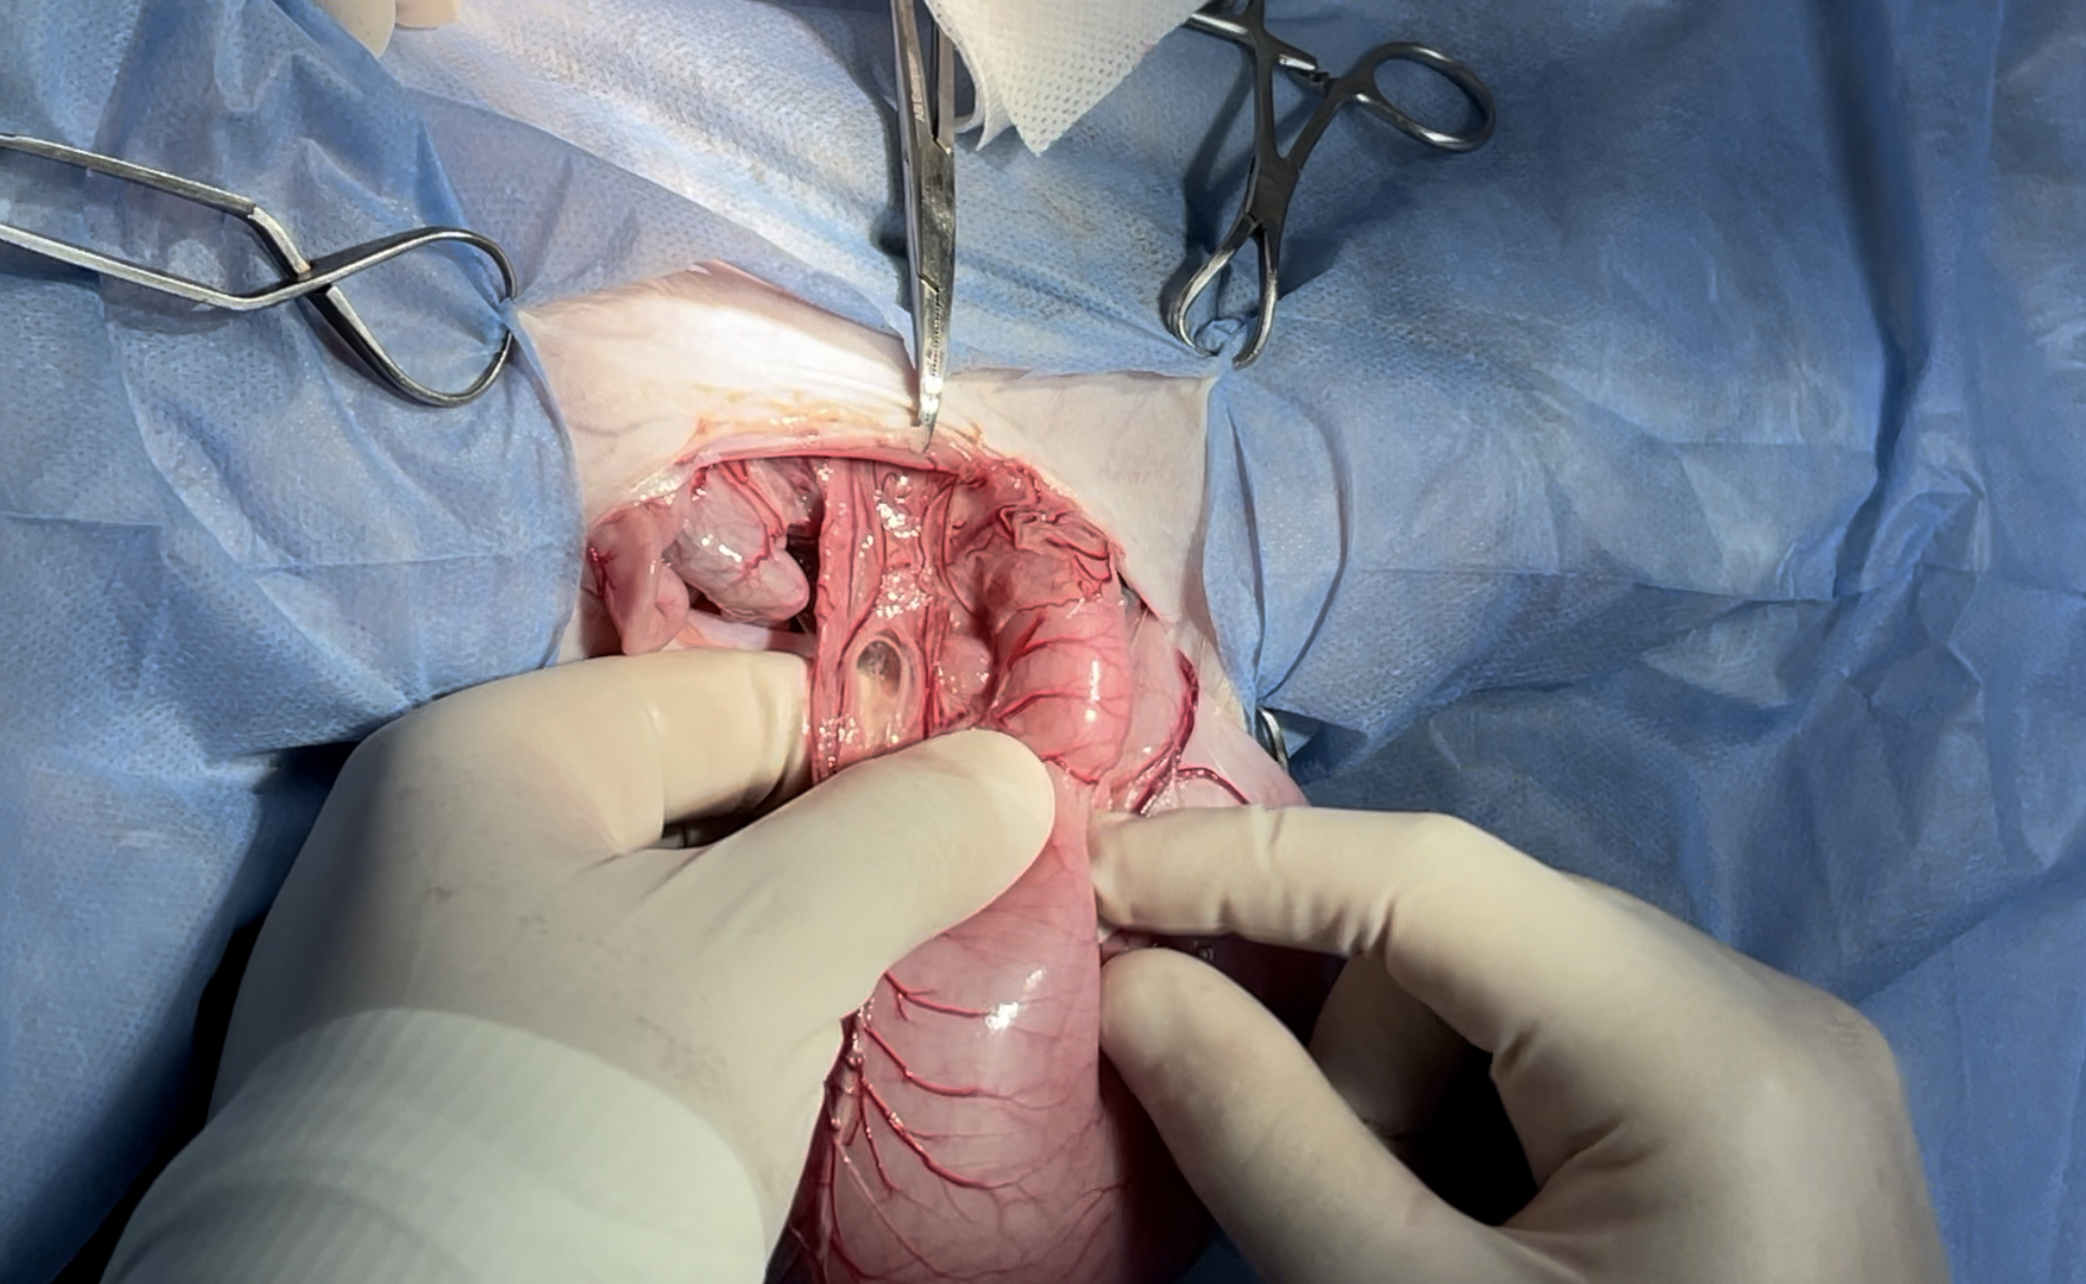

Surgical site extends from xyphoid to the umbilicus

Duodenal fb causing the obstruction

Lap sponge isolation prevents the contamination

Enterotomy incision was made for fb removal